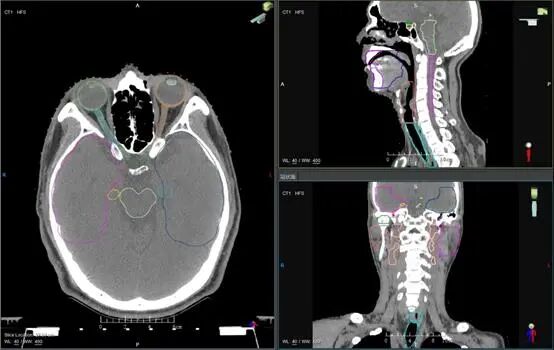

每当听到这样哭笑不得的对话时,放疗科的医生们就知道又“躺枪”了。忙碌的医生们真的是在打游戏吗?当然不是!医生们正在聚精会神进行一项非常重要并且非常精细的诊疗工作:在专业电脑上,利用专业的放射治疗计划系统,进行肿瘤靶区以及危及器官的精确勾画工作。用通俗的语言来讲,就是医生要在电脑上勾画出哪些区域是需要杀灭的“敌人”,哪些结构是需要保护的“朋友”。此项勾画工作是精准放疗的基础,所谓万丈高楼平地起,地基如果不牢靠,那么高楼就会变成危楼。医生有时需要聚精会神地盯着屏幕精细勾画数小时,是诊疗水平和工匠精神的充分体现。

放射治疗计划系统具有非常强大的功能:能够导入导出多模态图像、图像融合配准、肿瘤靶区和器官勾画、三维放疗 (3D-CRT) 计划设计、调强放疗 (IMRT) 计划设计等等。而患者有时看到的“玩游戏”,则是医生在放射治疗计划系统上进行肿瘤靶区和危及器官的勾画。

放疗医生通过仔细研判已经导入治疗计划系统软件中的患者CT、MRI等多模态影像,并根据患者个体情况,在患者定位CT/MRI图像上进行精确勾画,是整个精确放射治疗流程中最重要的基础。放疗医生就像是一个手艺精湛的“艺术家”,挥动手中如同画笔般的小鼠标,在放疗计划系统这块“画布”上,精确勾勒需要杀灭的肿瘤靶区和需要保护的危及器官。

完成精确勾画后,这块“画布”就传递到了放疗物理师的手中。物理师们按照肿瘤医生开具的放疗剂量处方,根据不同患者的具体病情,设计符合剂量要求的精确放疗计划。物理师像“雕刻师”一样,在放疗计划系统平台上,利用计划软件的逆向算法不断优化计算,将患者体内的剂量分布尽量“雕刻”成医生勾画出的形状。以达到靶区内剂量达标,而靶区外剂量尽量低的目标,这个过程需要临床医生和物理师细致沟通,甚至进行多次优化算法,微调照射剂量分布,最终实现“指哪打哪”和“剂量雕刻”的效果。